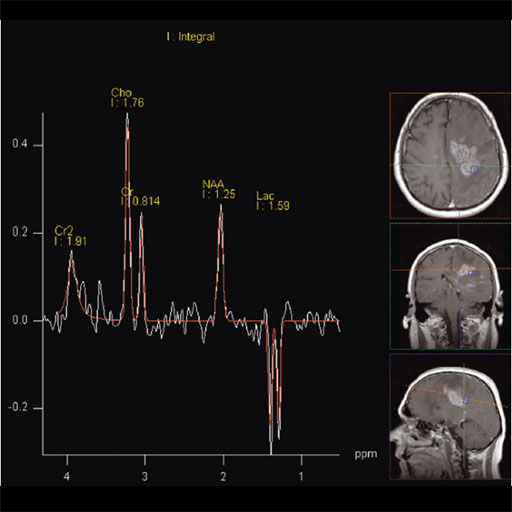

- 3D CSI (Chemical Shift Imaging):

Integrated multivoxel spectroscopy software package with

sequences and protocols for 3D Chemical Shift Imaging (CSI). Features Matrix Spectroscopy – phase-coherent signal combination from

several coil elements for maximum SNR with configurable

prescan-based normalization for optimal homogeneity 3D Chemical Shift Imaging Hybrid CSI with combined Volume selection and Field of View

(FoV) encoding Short TEs available (30 ms for SE, 20 ms for STEAM) Automized shimming of the higher order shimming channels for

optimal homogeneity of the larger CSI volumes Weighted acquisition, leading to a reduced examination time

compared to full k-space coverage while keeping SNR and

spatial resolution Outer Volume Suppression Spectral Suppression Protocols for prostate spectroscopy Clinical Applications Prostate Spectroscopy for diagnosis, localization of

prostate cancer Improved spatial localization of metabolic changes in biopsy

or radiotherapy planning

|

| Cho/Cr ratio map generated from

3D CSI measurement |

Spectral nap generated from 3D

CSI measurement |

Increased Cho-signal in a

medulloblastoma case |

Step by step: 1. Perform imaging in all three planes to include the entire

brain. Open the csi 3D se 135 sequence. Located in the exam

explorer in the Spectroscopy, CSI, head region. 2. Scroll thru the transversal images for area of interest.

3. Copy image position. Right click on the selected

transverse image, from the menu select copy image position.

4. Go to the scroll drop down menu and select scroll

nearest. This will align the 3D VOI in all three

orientations. 5. Rotate the VOI inplane on the transversal image to cover

the area of interest. 6. Open toolbar, and and select create sat bands. Draw

saturation bands around all sides of the 3D VOI to remove

lipid signal from calvarium. 7. Select fully excited VOI, on the Geometry card.

Apply the sequence.